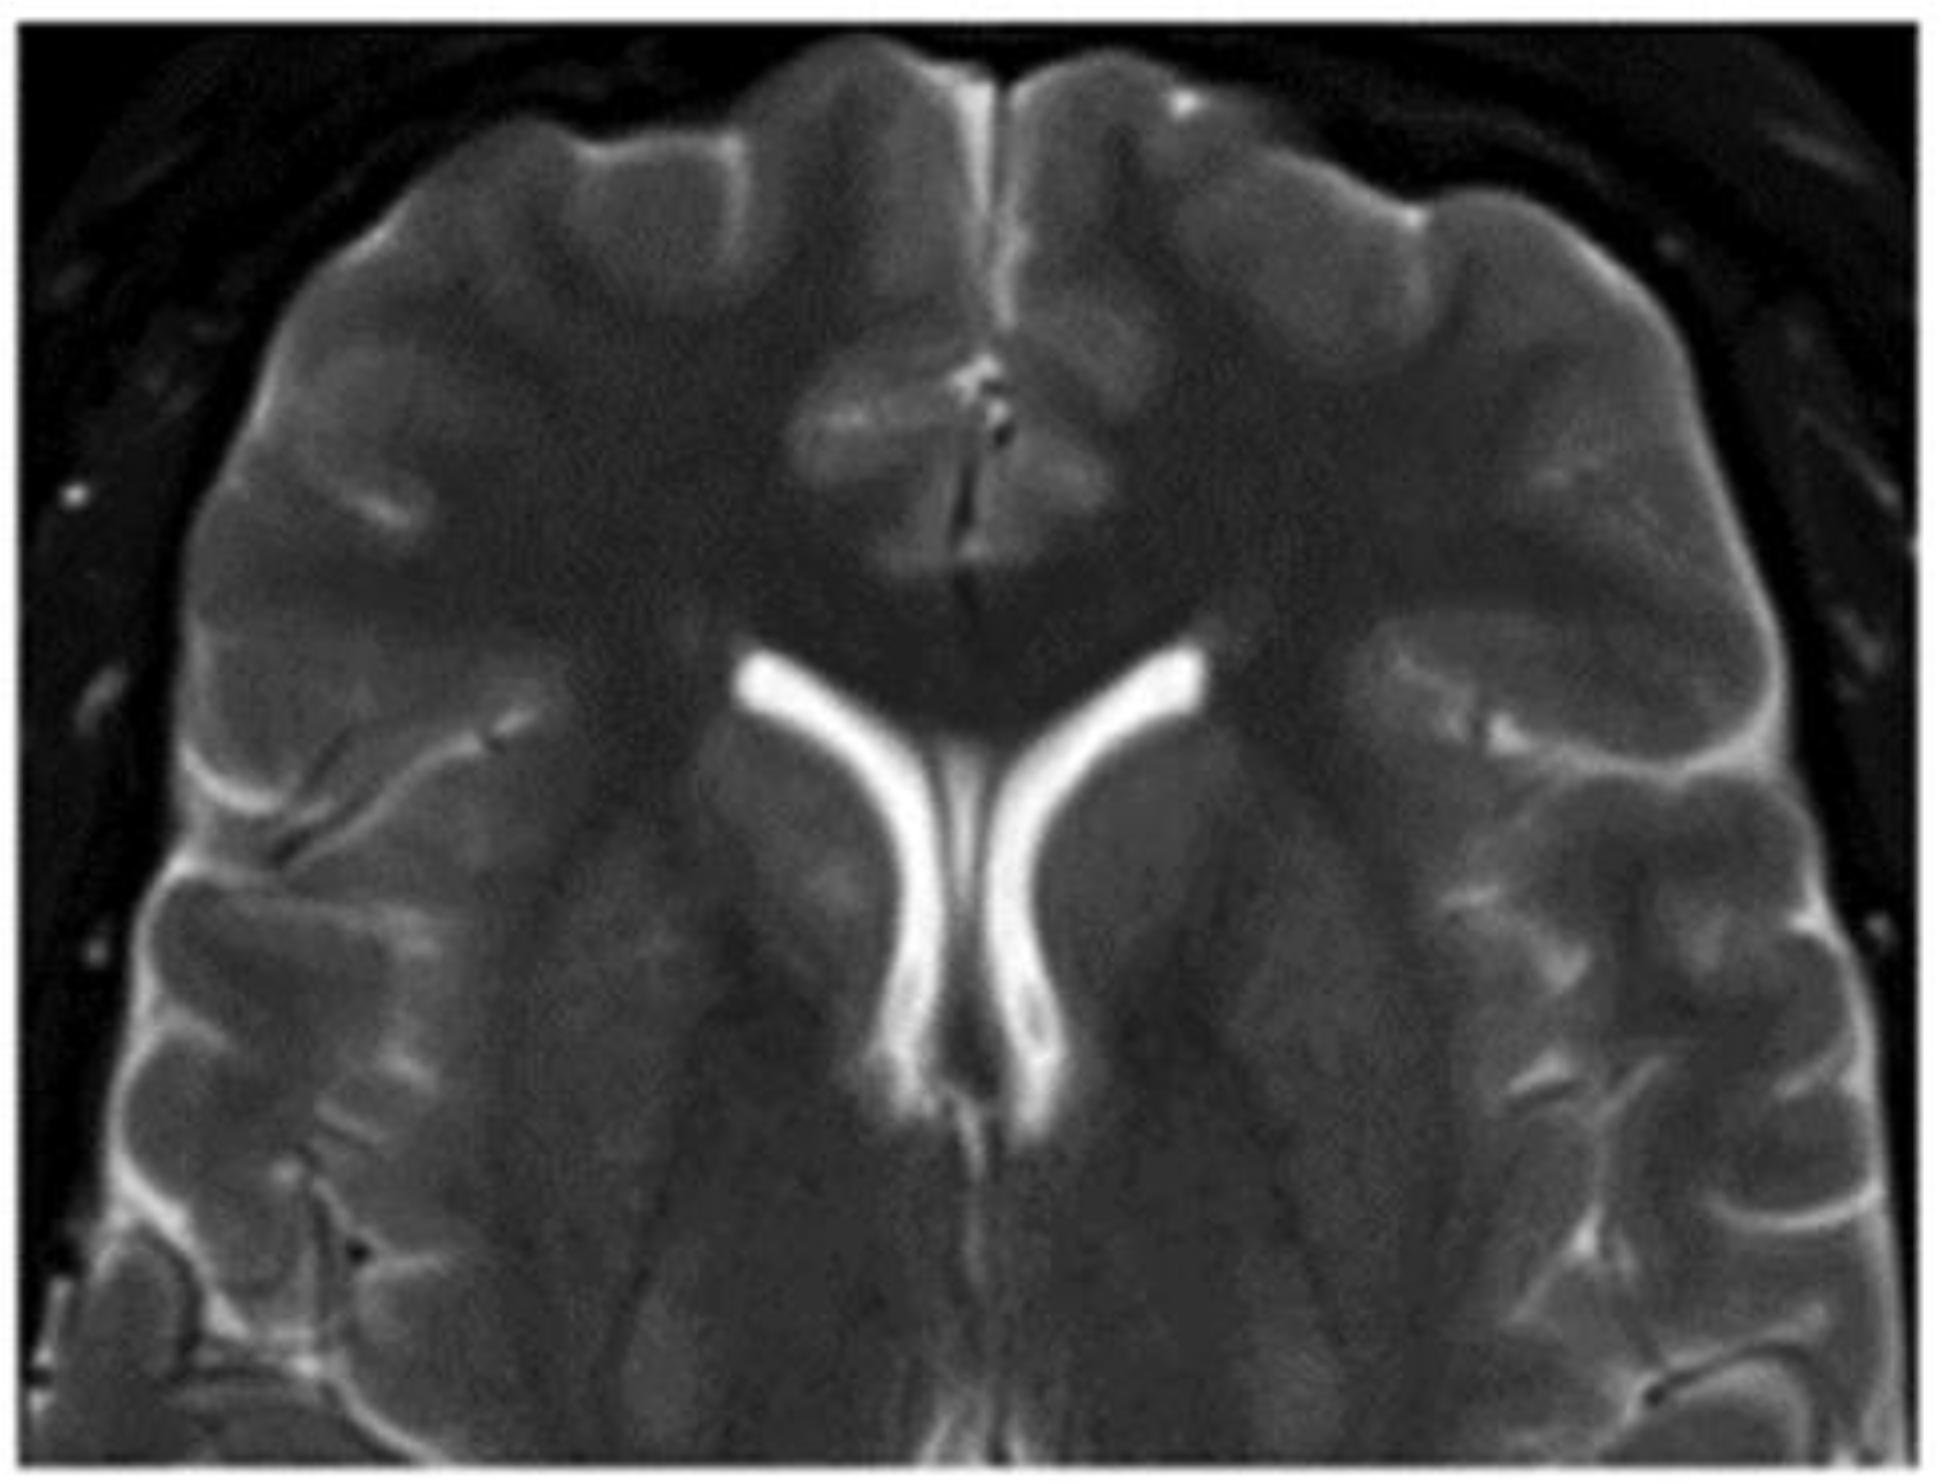

3.1.2. Brain Cavernous Angiomas

- Mokin, M.; Agazzi, S.; Dawson, L.; Primiani, C.T. Neuroimaging of Cavernous Malformations. Curr. Pain Headache Rep. 2017, 21, 47. [Google Scholar] [CrossRef]